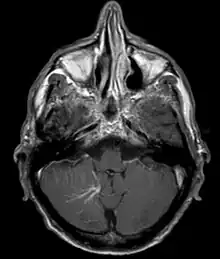

| Developmental venous anomaly in the cerebellum seen on axial contrast-enhanced T1 weighted MRI | |

A developmental venous anomaly (DVA, formerly known as venous angioma) is a congenital variant of the cerebral venous drainage. On imaging it is seen as a number of small deep parenchymal veins converging toward a larger collecting vein.